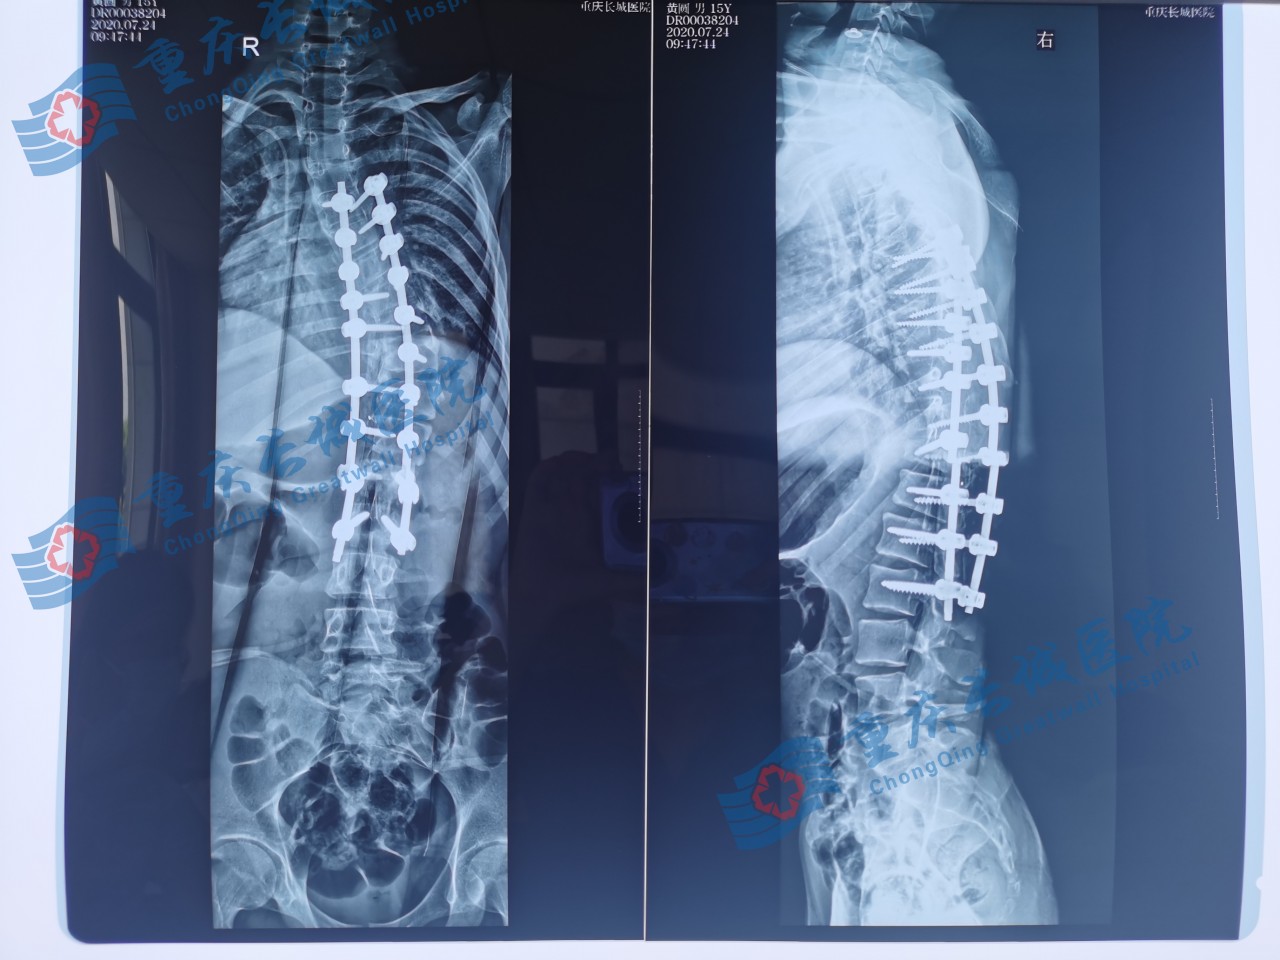

小圆术后

小圆的手术非常成功,侧弯的脊柱得到了有效的矫正,个子长高了5cm,体态发生了明显的变化,小伙子一下子就精神了,人也自信了。全家人对治疗效果都非常满意,激动地对医生表示感谢,让小圆能重获新生,健康成长,融入社会。